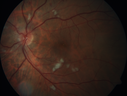

Grade 4 hypertensive retinopathy444 views55 year old man Hhe did have headaches a few weeks ago and also some nausea and vomiting. He noticed for a few weeks the vision in the left eye was blurred and that the vision in the left eye is dark.

VA OD: Dcc20/20

VA OS: Dcc20/100-1

He was admitted directly to ICU for blood pressure control (290 / 170 mmHg)

3 weeks later his VA increased to 20/20 OD, 20/32 OSJan 29, 2019